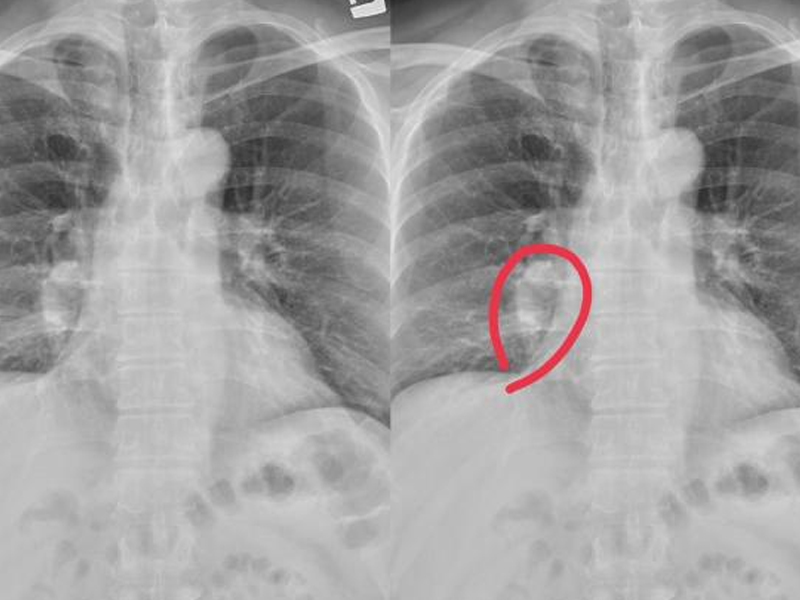

| 肺癌仍然是發病率和死亡率最高的惡性腫瘤,尤其是男性。具體病因不是很清楚,一般認為是遺傳的,吸煙或觸摸二手煙和油煙、環境、心理因素和其他相關因素。提到肺癌,人們必定會想到乾咳、咳血、胸悶、呼吸短促等,但並非所有肺癌患者都會呈現這種症狀,這可能表現為雙腿。假如你的腿有以下症狀,你需求儘快去醫院做低劑量的胸部螺旋 CT 篩查肺癌。  1. 雙腿皮膚反常 中醫說:肺主要是皮毛,所以你能夠通過皮膚狀況來判斷肺功用是否傑出。肺是氣體交換的重要器官,但也能運送氧氣。在肺功用正常的前提下,血液中有滿足的氧氣。但在肺癌變後,必然會影響肺功用,使腿部缺氧,導致腿部皮膚白色或紫色。 2. 長痣 腿上的痣問題不大,但短時間內增長敏捷,尤其是直徑大於 2cm 時,伴有痣破裂、膿液、邊界不清,需求高度懷疑肺癌。  3. 腿部浮腫 長期坐着或站着.喝太多的水很容易導致腿部水腫,但只要積極的改進能夠緩解。假如腿部繼續水腫,按壓後反彈速度較慢,首先排除腎病,但也需求警惕肺癌。因為癌細胞的快速增殖速度,它能夠耗費體內的大部分能量,這很容易導致細胞浸透壓力失衡,使水逐漸浸透到細胞組織中。隨着癌細胞的擴散,它能夠壓榨下肢血管或神經,然後導致繼續的水腫,肺癌越嚴峻,水腫問題就越顯着。 4. 關節痛苦 許多肺癌患者在發病期間會呈現難以忍受的腿部痛苦,尤其是在行走時。因為癌細胞在增殖過程中能夠吸收肺部養分,也能夠轉移到其他部位。骨骼和關節首戰之地,因為骨骼中有豐富的血液和促進癌細胞生長的因素。 |